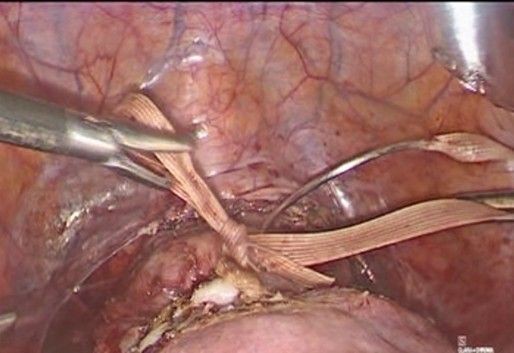

- Preparation and access (Figure 2): The patient is placed in a modified dorsal lithotomy position, with a slight Trendelenburg position to facilitate pelvic exposure. Pneumoperitoneum is installed through the Palmer point access, and trocars are placed. The abdominal and pelvic cavities are assessed, identifying the uterus, adnexa, bladder, and rectum.

Figure 2: preparation and access at Palmer’s point